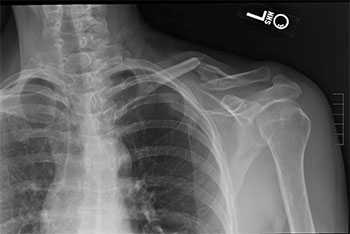

Photo Courtesy of Aaron Mark Chamberlain, MD, MSc, MBA, FAAOS